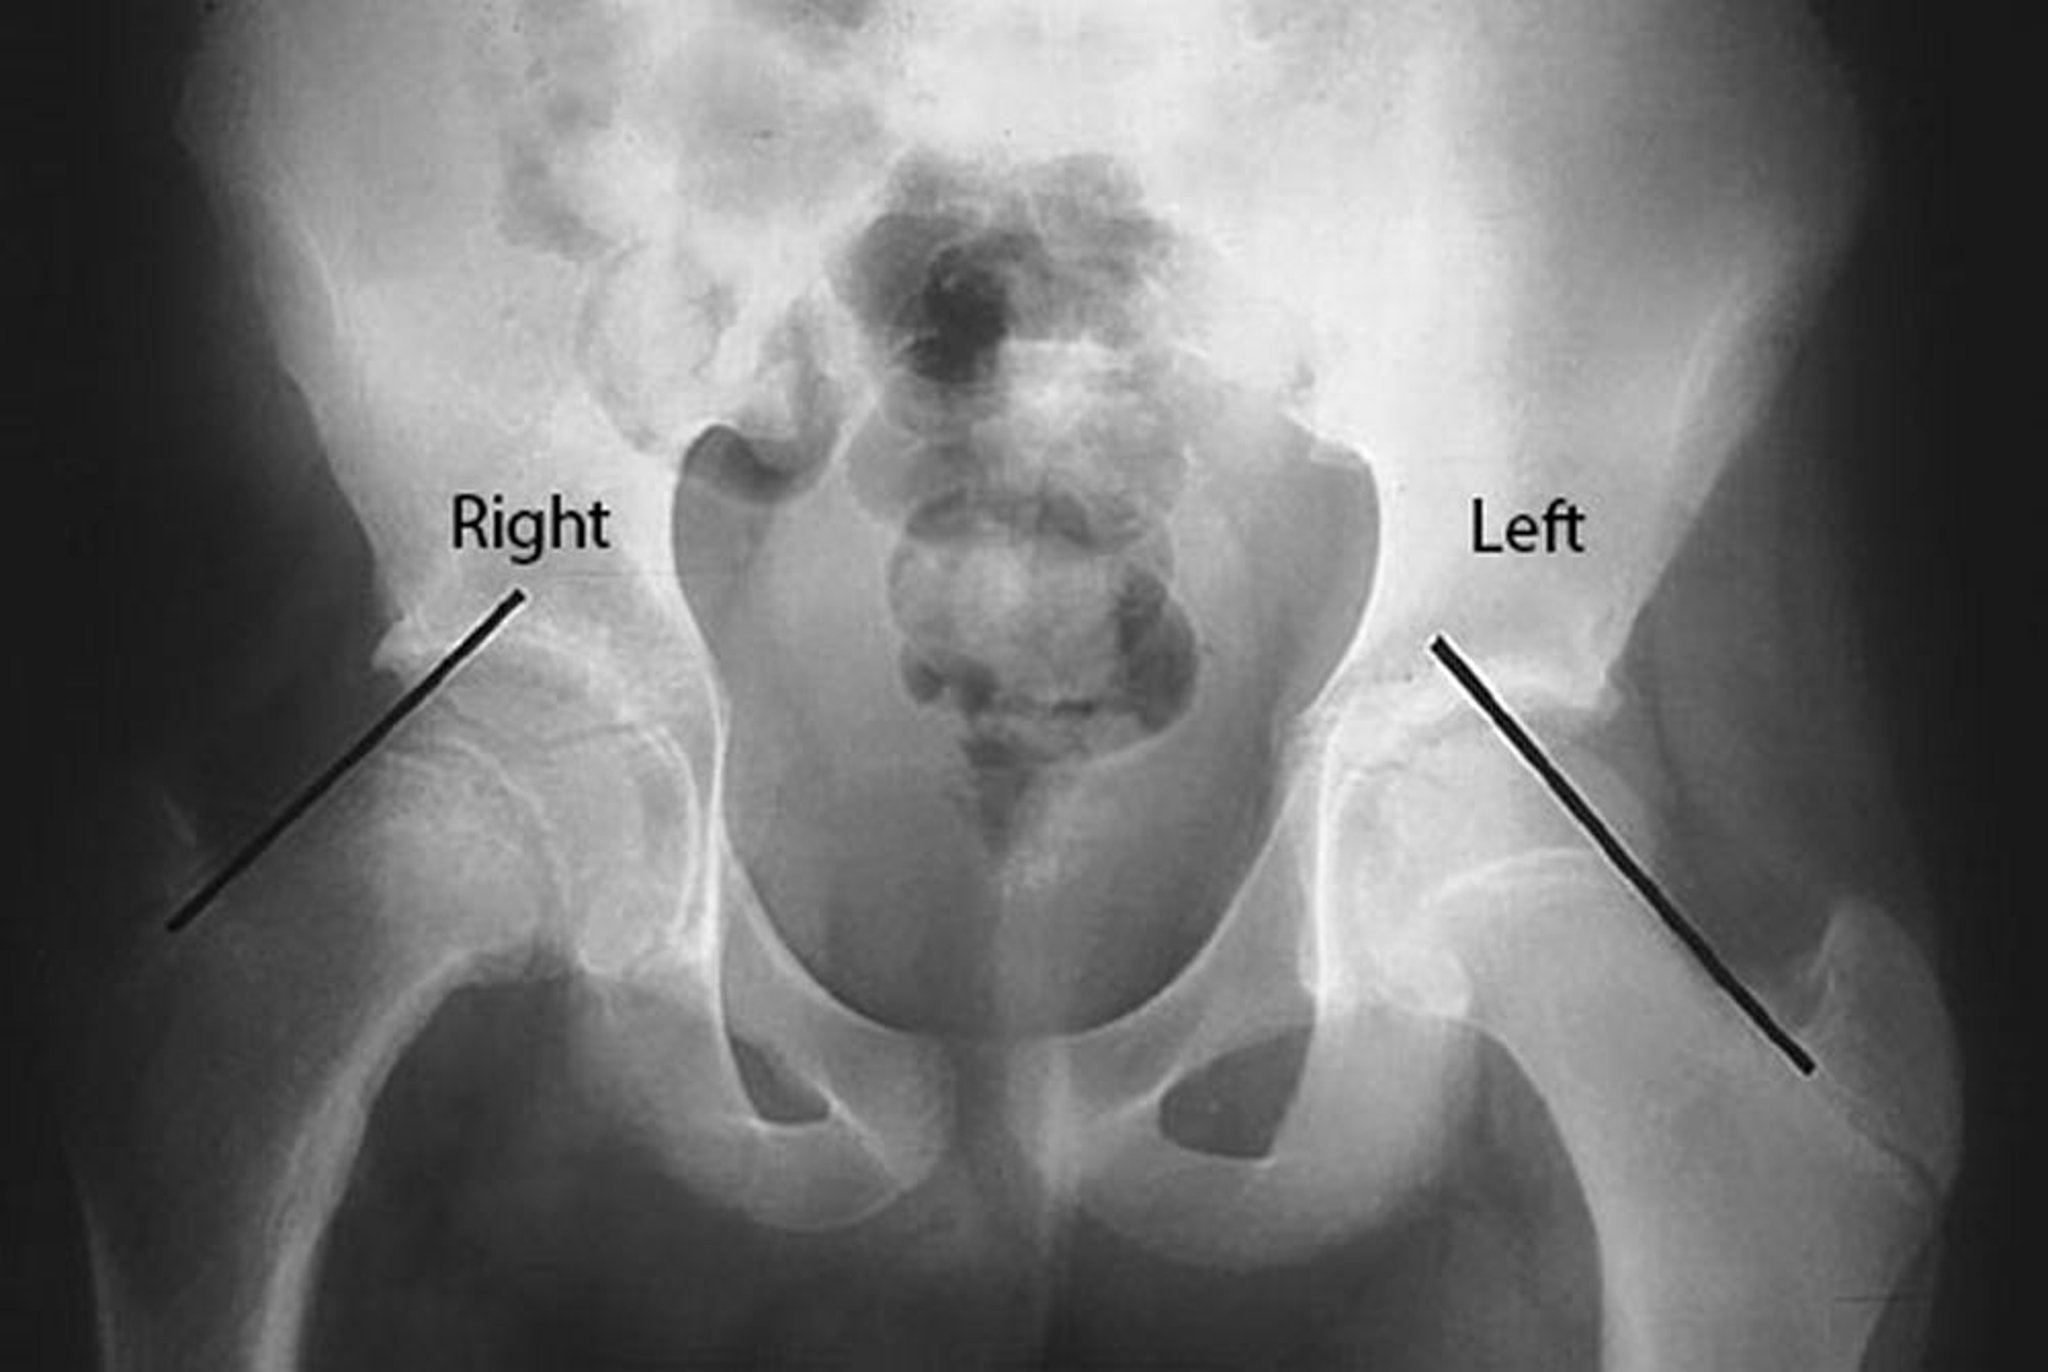

Epifisiólisis femoral superior

Se dibujan las líneas de Kline en el borde superior del cuello femoral en este paciente con desplazamiento de la epífisis de la cabeza femoral. Obsérvese que del lado afectado, el derecho, la cabeza femoral está por debajo de la línea de Klein, mientras que del lado no afectado, una parte importante de la cabeza femoral se halla por encima de la línea de Klein.

By permission of the publisher. From Campbell R Jr: Current Orthopedic Diagnosis and Treatment. Publicado por JD Heckman, RC Schenck, and A Agarwal. Philadelphia, Current Medicine, 2002.